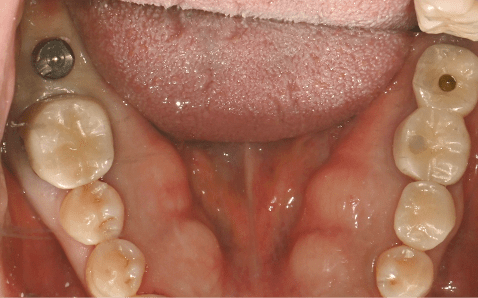

Case 02

Before Implant Placement Right After Flapless Implant Placement

Photo Date : 2024.06.19